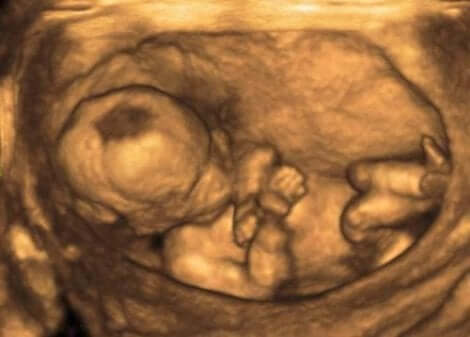

Legepersonell oppdager vanligvis disse endringene ved hjelp av en ultralydprosedyre for å måle volumet av fostervann. De gjør det gjennom fostervannindeksen (AFI).

For å få denne informasjonen deler eksperten livmoren i fire uhindrede kvadranter, som de måler i centimeter. En normal AFI er mellom 3 og 8 tommer (8 og 21 cm).